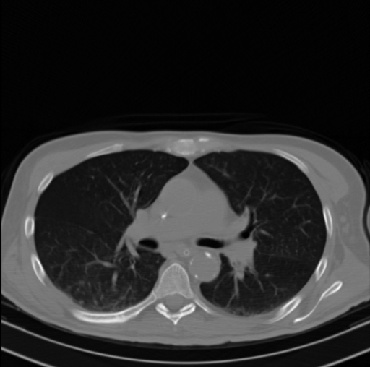

Early and reliable COVID-19 diagnosis based on chest 3-D CT scans can assist medical specialists in vital circumstances. Deep learning methodologies constitute a main approach for chest CT scan analysis and disease prediction. However, large annotated databases are necessary for developing deep learning models that are able to provide COVID-19 diagnosis across various medical environments in different countries. Due to privacy issues, publicly available COVID-19 CT datasets are highly difficult to obtain, which hinders the research and development of AI-enabled diagnosis methods of COVID-19 based on CT scans. In this paper we present the COV19-CT-DB database which is annotated for COVID-19, consisting of about 5,000 3-D CT scans, We have split the database in training, validation and test datasets. The former two datasets can be used for training and validation of machine learning models, while the latter will be used for evaluation of the developed models. We also present a deep learning approach, based on a CNN-RNN network and report its performance on the COVID19-CT-DB database.